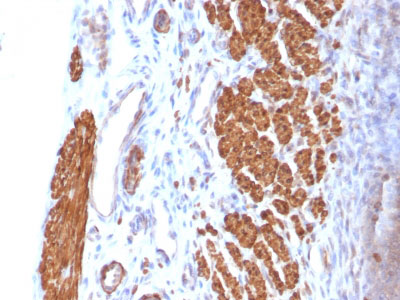

Formalin-fixed, paraffin-embedded Rat Uterus stained with Calponin-1 Monoclonal Antibody (CNN1/832). |